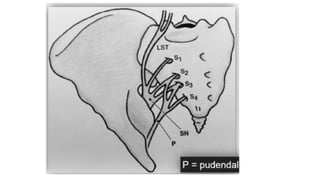

● Neurologic

○ Lumbosacral trunk- anterior to the sacral ala and SI joint

○ 2cm medial to the SI joint

● Neurologic ○ Lumbosacraltrunk- anterior to the sacral ala and SI joint ○ 2cm medial to the SI joint